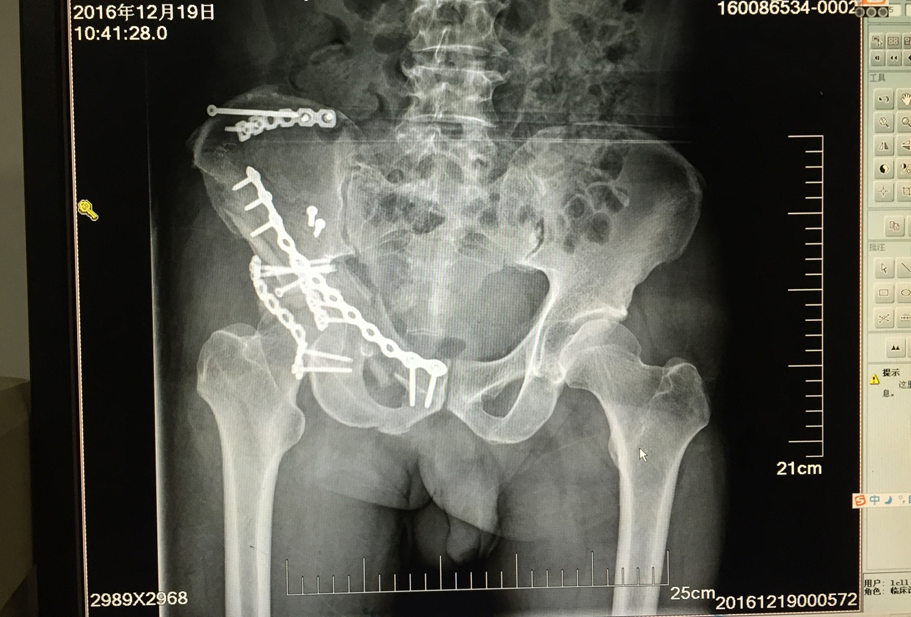

科室主任贾晋辉博士先后两次赴德国学习,在骨折微创手术,全髋关节置换,全膝关节置换,膝关节单髁置换、关节镜微创手术等方面引进当今最先进技术,已治愈了几千例患者,病人满意度很高。

中西医结合治疗骨折是本科的特色;除了运用最先进的手术技术,科室还开展最传统的手法复位小夹板外固定技术,配合自行研发的中药外敷,给患者更好、更多的选择,小夹板固定和骨折微创技术治疗四肢骨折,疗效好,恢复快,效果达到国内先进水平。